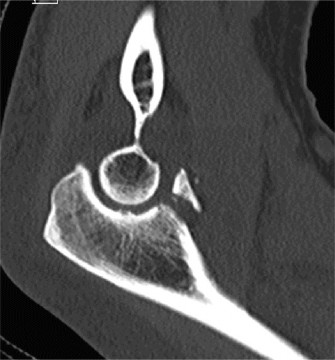

It should be noted that reverse total shoulder arthroplasty is also the procedure of choice in patients with cuff-tear arthropathy (aka rotator cuff arthropathy). Characteristics of cuff-tear arthropathy include superior migration of the humerus due to a massive rotator cuff tear, glenohumeral joint destruction, subchondral osteoporosis, and humeral head collapse (see Fig. 2–17). A reverse total shoulder

Figure 2–17_X-rays of a patient showing evidence of cuff tear arthropathy. The humerus is migrated superiorly, the glenohumeral joint is destroyed, there is subchondral osteoporosis, and the humeral head is collapsed. (From Ecklund KJ, Lee TQ, Tibone J, Gupta R. Rotator cuff tear arthropathy. _J Am Acad Orthop Surg. 2007;15(6):340–349.)